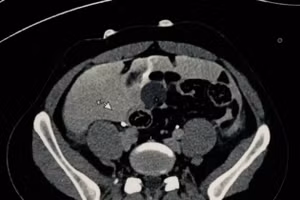

Hình ảnh chụp CT của bệnh nhân. Ảnh: BVCC.

Nam thanh niên vỡ bàng quang sau cuộc nhậu

GD&TĐ - Khoa Ngoại Tổng hợp, Bệnh viện Bạch Mai vừa tiếp nhận và điều trị một ca bệnh hy hữu. Bệnh nhân bị vỡ bàng quang dẫn đến viêm phúc mạc sau một “trận bia” cùng bạn bè.